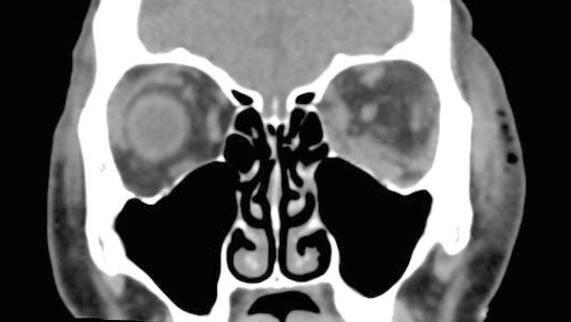

En octubre de 2019, el paciente fue referido a nuestro servicio para evaluación por disminución de la AV; (AV mejor corregida AVMC 6/10 OD y 10/10 OI). En la biomicroscopía (BMC) como se observa en las figuras 1 y 2 de ambos ojos (AO) se constataron precipitados queráti-

cos (PKs) intermedios a gruesos, difusos, células en cámara anterior de 3x y sinequias posteriores (SP). La presión intraocular (PIO) era de 40/20 mm Hg en OD y en OI respectivamente. En el fondo de ojos (figuras 3 y 4) se constató palidez de papila y atrofia peripapilar, retina

Figuras 1 y 2: biomicroscopía de ambos ojos: precipitados queráticos (PKs) intermedios a gruesos, difusos, células en cámara anterior de 3x y sinequias posteriores (SP). Figuras 3 y 4: fondo de ojos derecho e izquierdo: palidez de papila y atrofia peripapilar, retina aplicada y despigmentación difusa (sunset glow fundus).